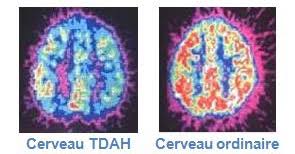

■ Le diagnostic médical sera fait dans la plupart des pays francophones sur la base de 2 à 3 entretiens avec un psychiatre ou un neurologue. Le TDAH peut être mis aussi en évidence par une IRM (images des deux cerveaux ci-dessous), même si cela n’a pas valeur de diagnostic.